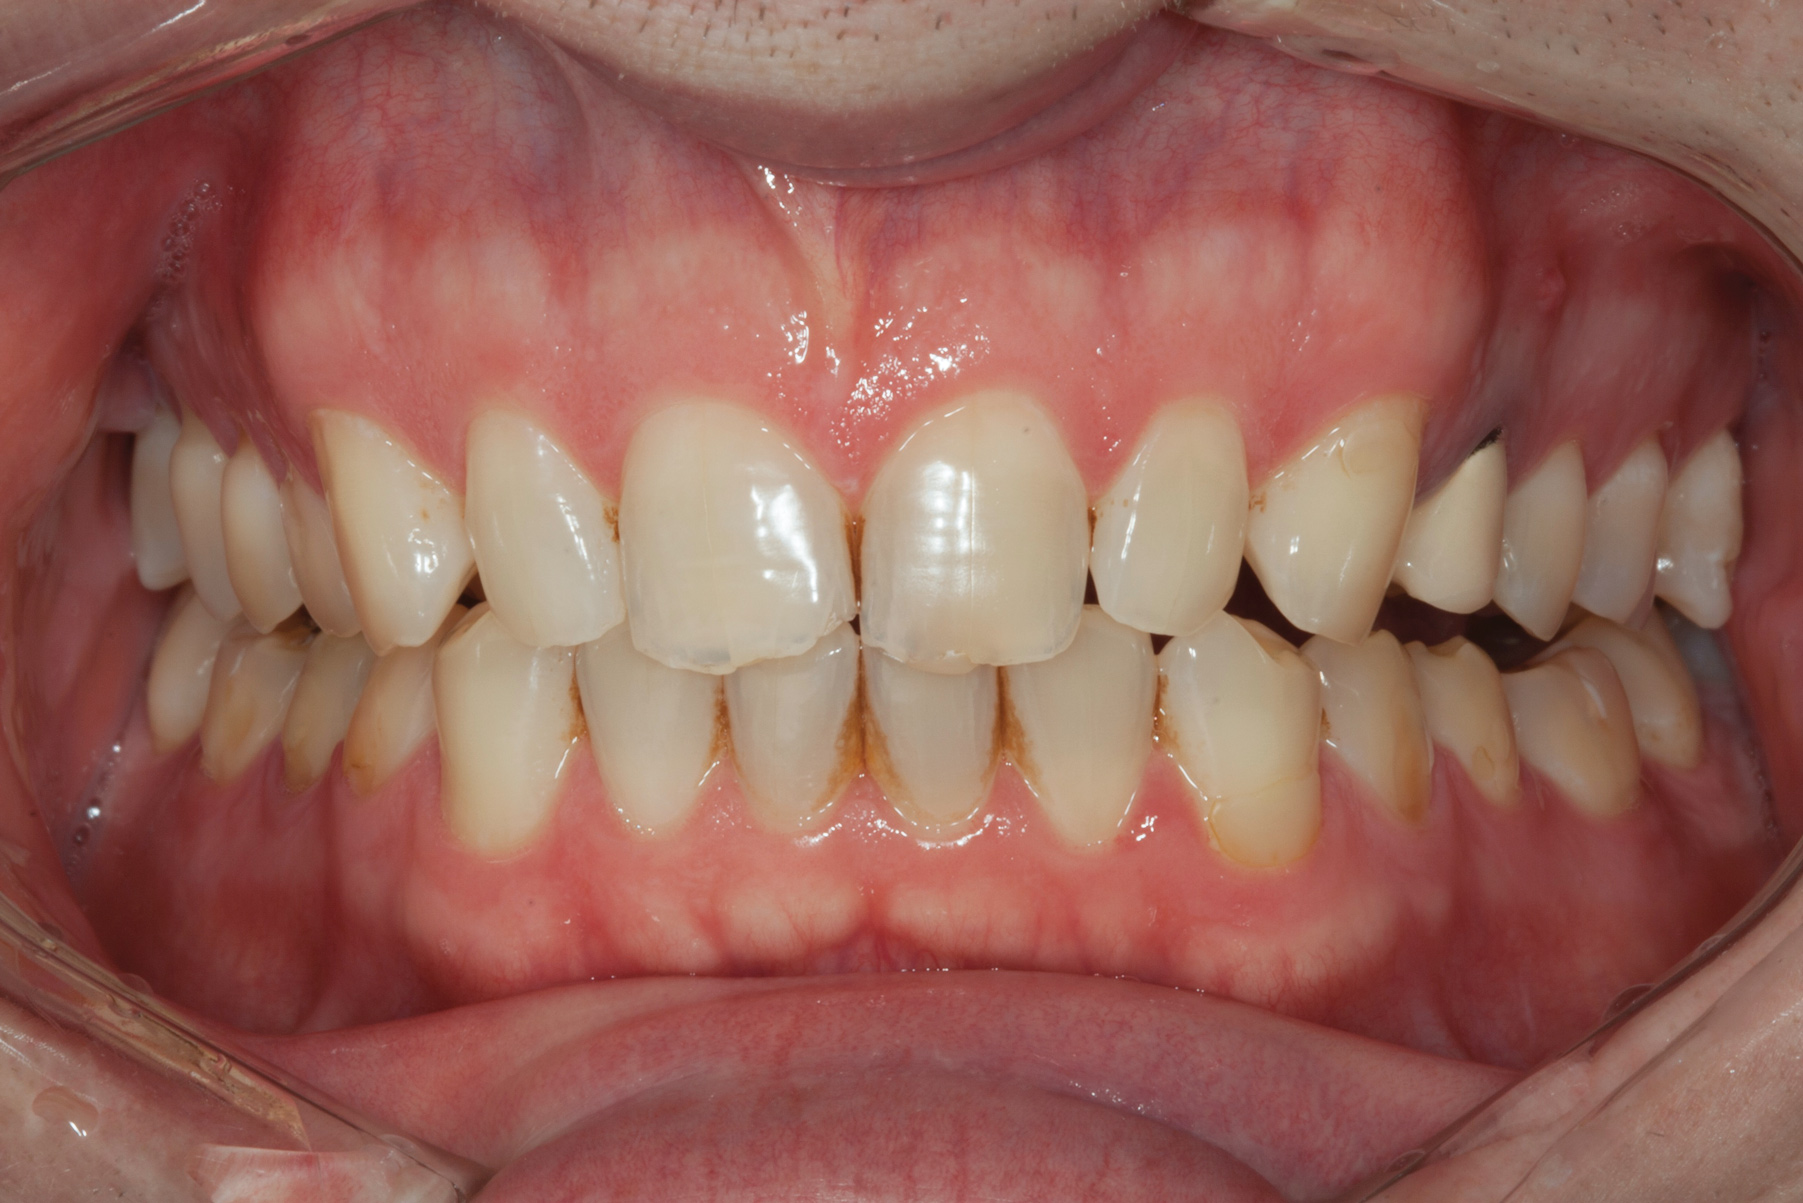

(2.) Preoperative retracted view.

Figure 2